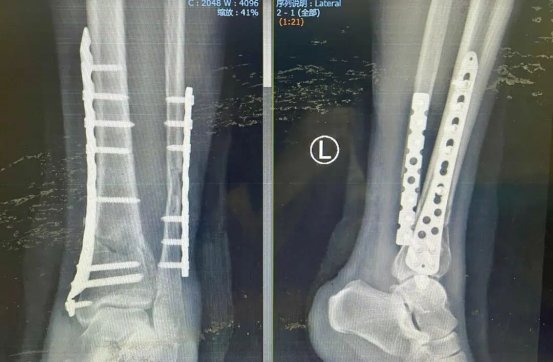

术后影像图

接诊后,刘毅团队迅速为柯女士进行三维CT检查,精准评估骨折移位与关节面损伤情况。考虑到患者年轻、对运动功能恢复要求高,团队制定了“微创复位内固定术”方案,采用MIPPO技术通过小切口植入钢板螺钉,最大程度保留关节活动功能。

术后,团队为柯女士量身定制康复计划,从被动活动到逐步负重,有序推动功能恢复。术后三周,她已能平稳行走。医生表示,通过后续系统训练,不久后柯女士有望重返雪场。